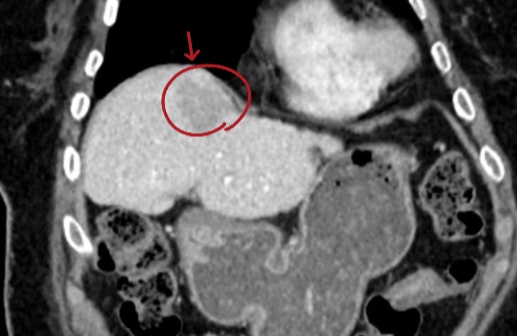

患者术前CT

利用术前CT,进行三维重建。